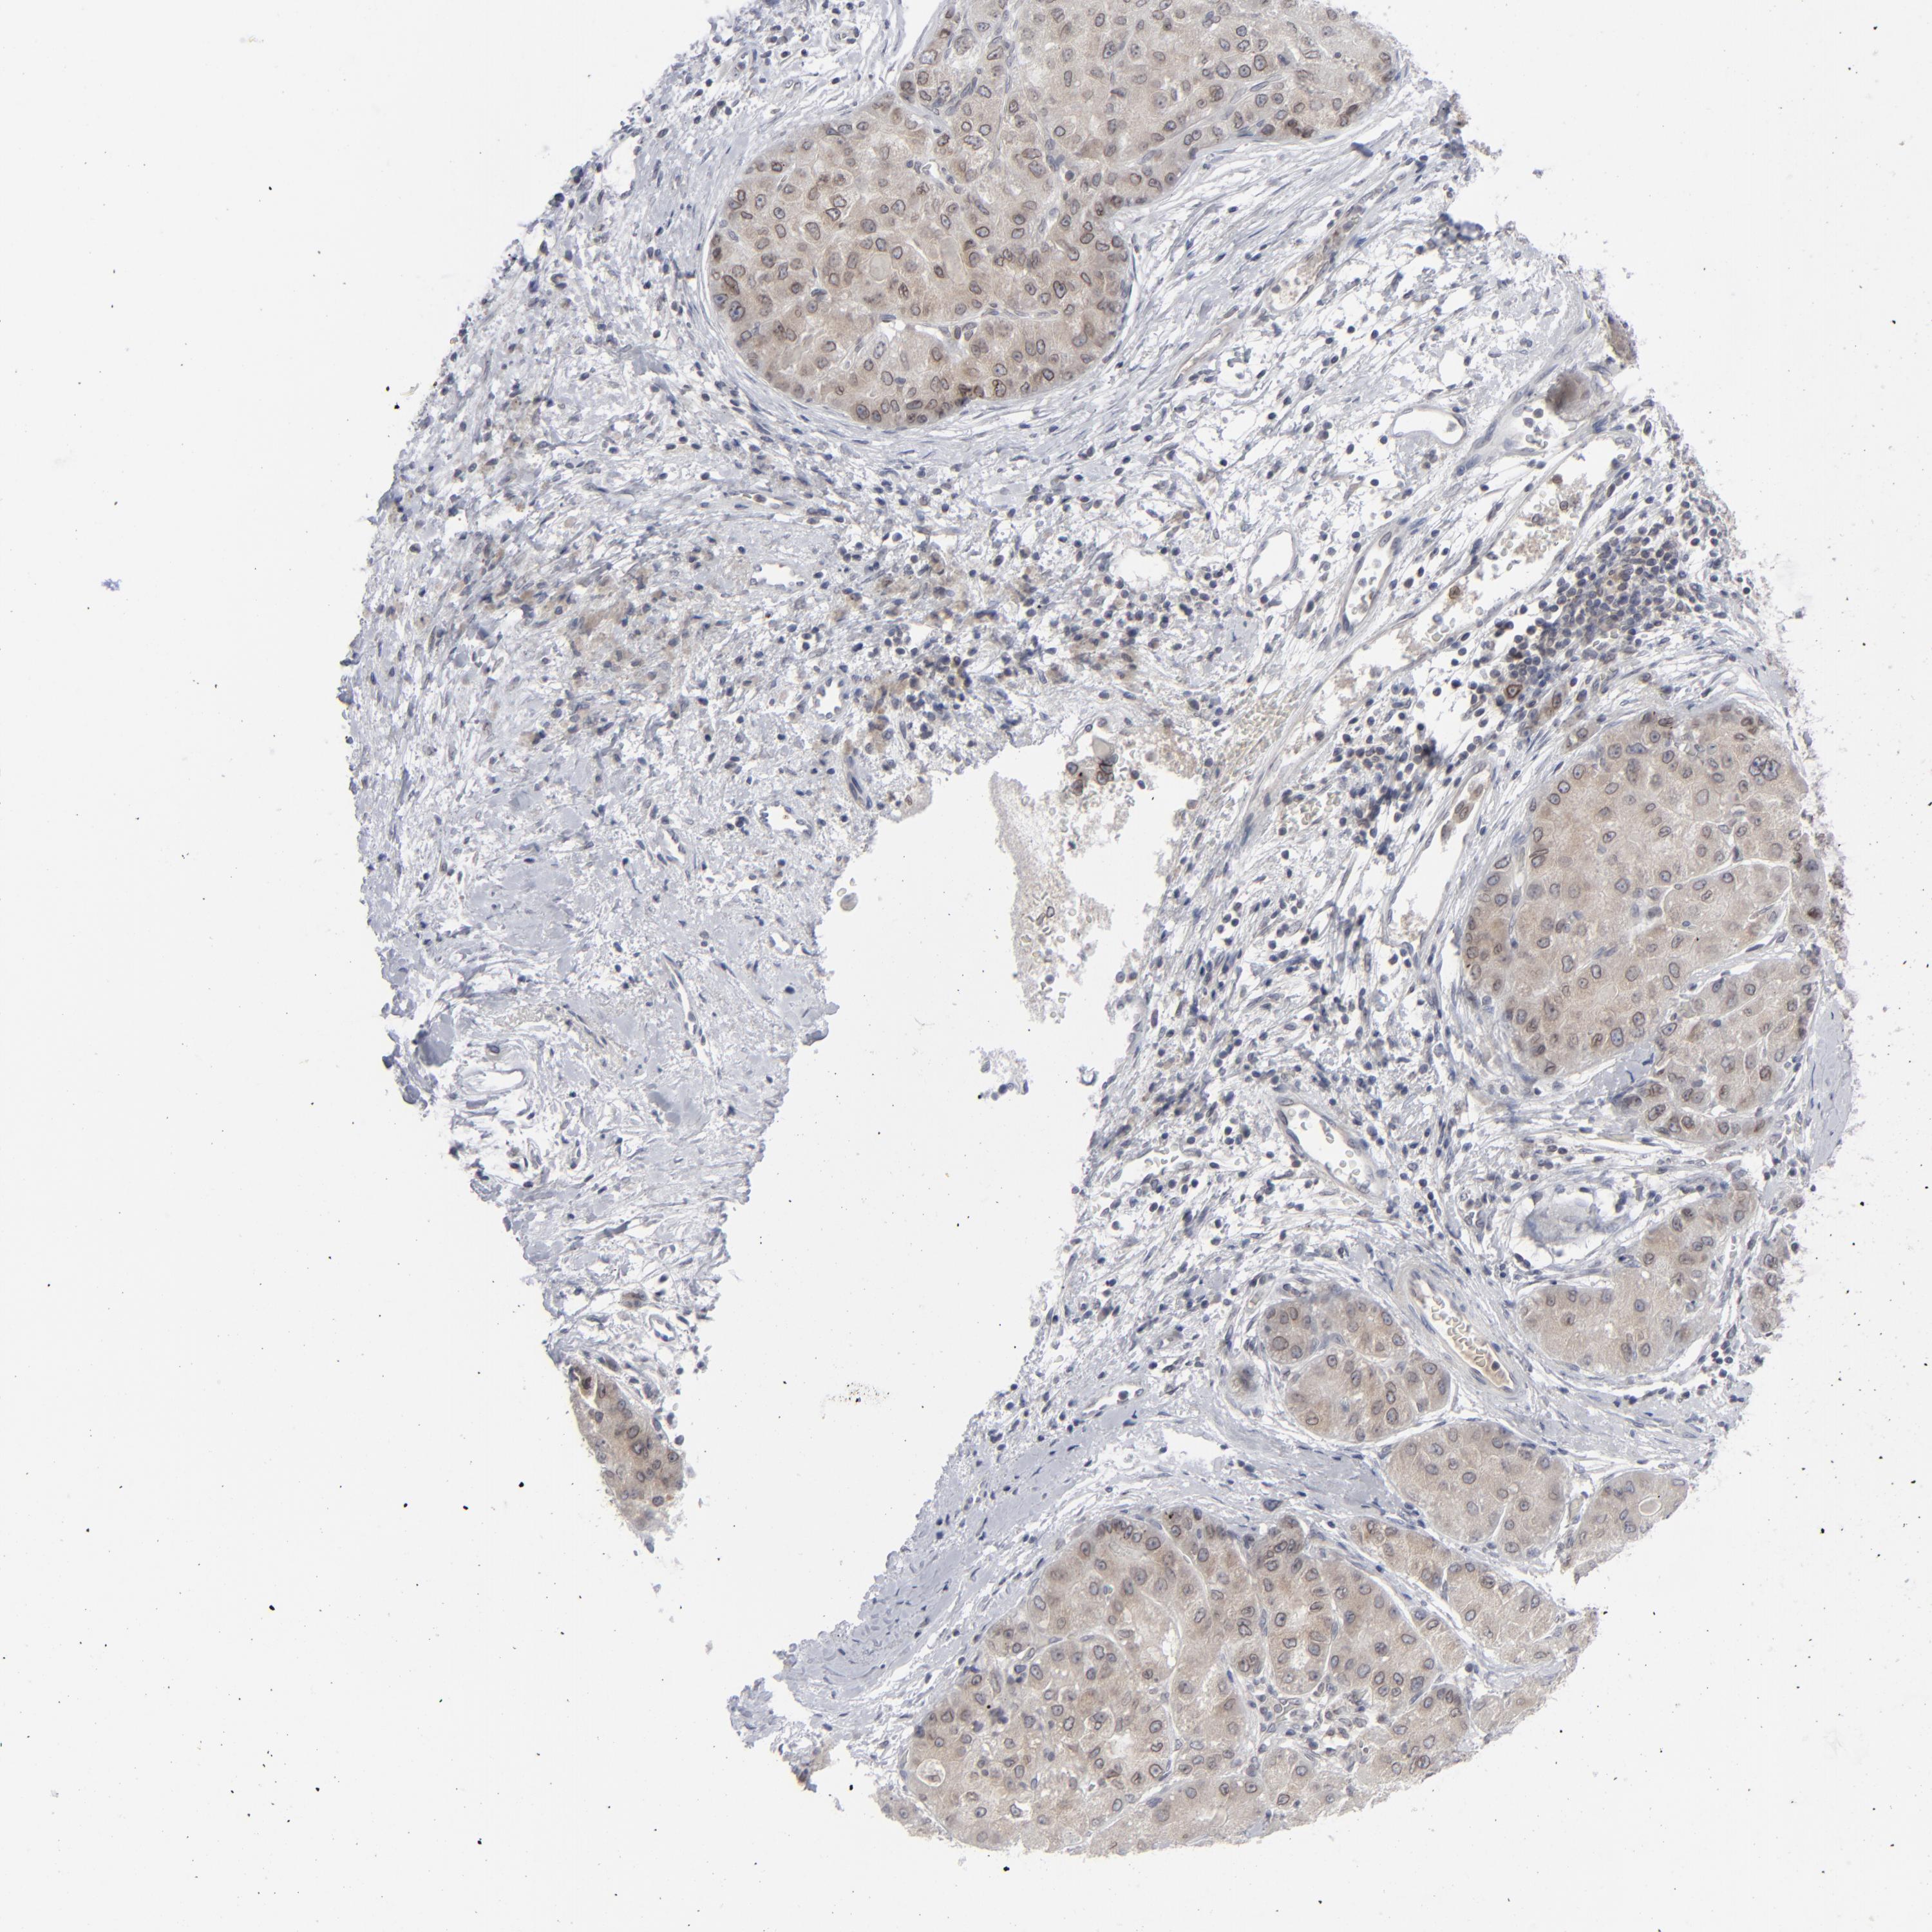

LIVER CANCER - Protein expressioni

A mouse-over function shows sample information and annotation data. Click on an image to view it in a full screen mode. Samples can be filtered based on level of antibody staining by selecting one or several of the following categories: high, medium, low and not detected. The assay and annotation is described here.

Note that samples used for immunohistochemistry by the Human Protein Atlas do not correspond to samples in the TCGA dataset.

Antibody stainingi

Antibody staining in the annotated cell types in the current human tissue is reported as not detected, low, medium, or high, based on conventional immunohistochemistry profiling in selected tissues. This score is based on the combination of the staining intensity and fraction of stained cells.

Each image is clickable and will lead to virtual microscopy that enables deeper exploration of all samples and also displays staining intensity scores, fraction scores and subcellular localization as well as patient and tissue information for each sample.

Antibody HPA021816

Antibody CAB002209

Staining

High

Medium

Low

Not detected

Intensity

Strong

Moderate

Weak

Negative

Quantity

>75%

75%-25%

<25%

None

Location

Nuclear

Cytoplasmic/membranous

Cytoplasmic/membranous,nuclear

Cholangiocarcinoma

Carcinoma, Hepatocellular, NOS